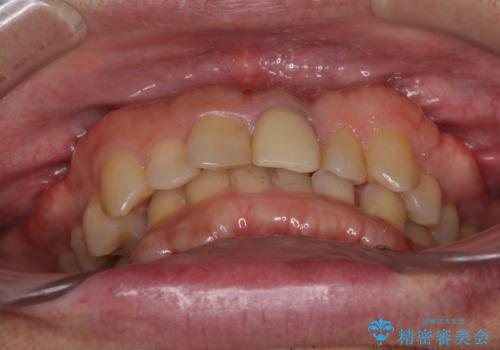

インビザラインによる治療を希望されたため、左側のスペースは閉じ、右側はスペースをより拡大し、インプラント補綴を行うこととしました。

咬合力が強く、インビザラインのみではディープバイトを改善することができず、半年間ほどワイヤー装置による矯正治療を行いました。

インプラントの埋入は矯正治療中に行い、矯正治療後はインプラント上補綴および、前歯のセラミック治療を行いました。